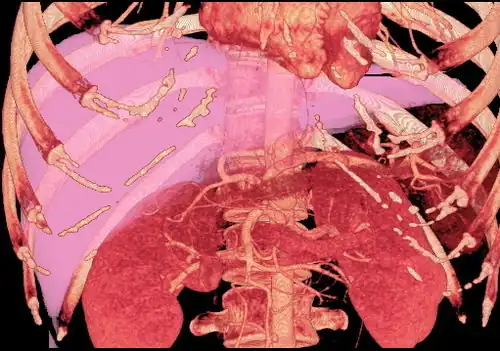

With the recent advances of noninvasive imaging, living liver donors usually have to undergo imaging examinations for liver anatomy to decide if the anatomy is feasible for donation. The evaluation is usually performed by multidetector row computed tomography (MDCT) and magnetic resonance imaging (MRI). MDCT is good in vascular anatomy and volumetry. MRI is used for biliary tree anatomy. Donors with very unusual vascular anatomy, which makes them unsuitable for donation, could be screened out to avoid unnecessary operations.

MDCT image. 3D image created by MDCT can clearly visualize the liver, measure the liver volume, and plan the dissection plane to facilitate the liver transplantation procedure. -